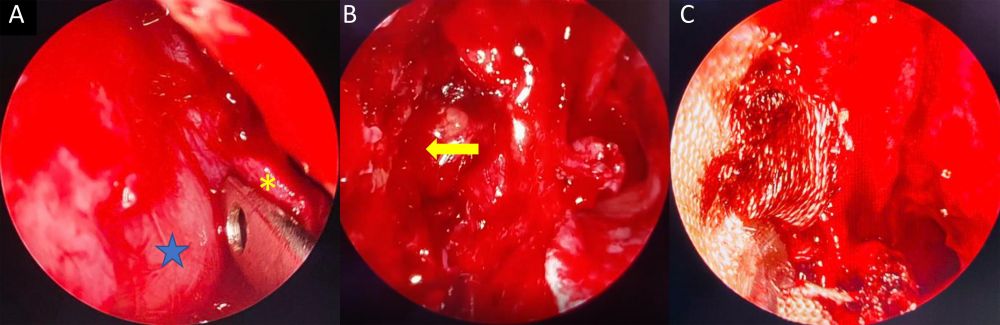

Với kỹ thuật phẫu thuật mới kết hợp sử dụng mũi khoan kim cương, phẫu thuật viên có thể đưa dụng cụ vào trong xoang một cách thuận lợi, đồng thời tăng khả năng quan sát và tiếp cận để xử trí các khối u nằm ở thành trước dưới hoặc thành trong dưới của xoang hàm. Việc khoan mở thành trong dưới xoang hàm giúp các thao tác phẫu thuật được thực hiện dễ dàng hơn nhờ phẫu trường rộng và cho phép sử dụng dụng cụ linh hoạt. Ngoài ra, kỹ thuật này còn giúp mở rộng lỗ thông xoang hàm, tạo điều kiện thuận lợi cho việc súc rửa và vệ sinh lòng xoang sau mổ, từ đó góp phần thúc đẩy quá trình lành thương.

Hình 2. Hình ảnh khối u trong mổ. A, Khối u (hình ngôi sao) đẩy dồn ống lệ tỵ (hình hoa thị) vào trong khiến bệnh nhân chảy nước mắt; B, Khối u làm tiêu xương thành sau xoang hàm (mũi tên vàng), bộc lộ động mạch hàm trong và mỡ hố dưới thái dương; C, Lấy sạch khối u và đặt vật liệu cầm máu tự tiêu.

Hậu phẫu, bệnh nhân hồi phục tốt với chức năng thở mũi hoàn toàn bình thường, không ghi nhận biến dạng vùng mặt và không cần đặt nhiều vật liệu cầm máu; thời gian nằm viện được rút ngắn còn 1–2 ngày. Kỹ thuật này cho thấy tính an toàn và hiệu quả cao nhờ khả năng tiếp cận trực tiếp tổn thương với mức độ xâm lấn tối thiểu.